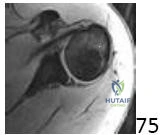

A 28-year-old semi-professional baseball pitcher presents with recurrent anterior glenohumeral instability despite dedicated rehabilitation. He has suffered 5 dislocations in the past 18 months. An axial CT scan reveals a glenoid bone loss of approximately 28% and an engaging Hill-Sachs lesion. The image provided shows a representative axial CT view of a shoulder with bone loss.